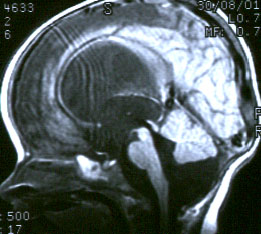

Диагностика: На настоящий момент МРТ головного мозга является методом выбора при диагностике данной патологии. Следует отметить, что кроме МРТ головного мозга при подозрении на аномалию Киари-1 необходимо сделать МРТ шейного и грудного отделов спинного мозга для исключения/подтверждения сирингомиелии. И, наоборот, при наличии сирингомиелии в обязательном порядке необходимо сделать МРТ головного мозга с особым вниманием на состояние структур ЗЧЯ.

“Расщепленный спинной мозг” – выделяют два варианта этой патологии: диастематомиелия – когда костный “шип” (см.МРТ изображение) разделяет как спинной мозг, так и дуральный мешок на два отдельных “рукава”; дипломиелия – когда сам спинной мозг разделен на две половинки фиброзным тяжом и, все это находится в едином дуральном мешке. Симптоматика, показания к операции и результаты аналогичны описанным выше в разделе “Фиксированный спинной мозг” (“tethetred cord”). Операция состоит из “удаления шипа” и освобождения спинного мозга (“untethering”) путем иссечения конечной нити.

Диагностика: кроме визуального осмотра перед планированием операции необходимо сделать МРТ головного мозга в 3-х проекциях. Это позволит визуализировать содержимое мешка (мозг, синусы, магистральные сосуды), планировать объем операции и прогнозировать исход.